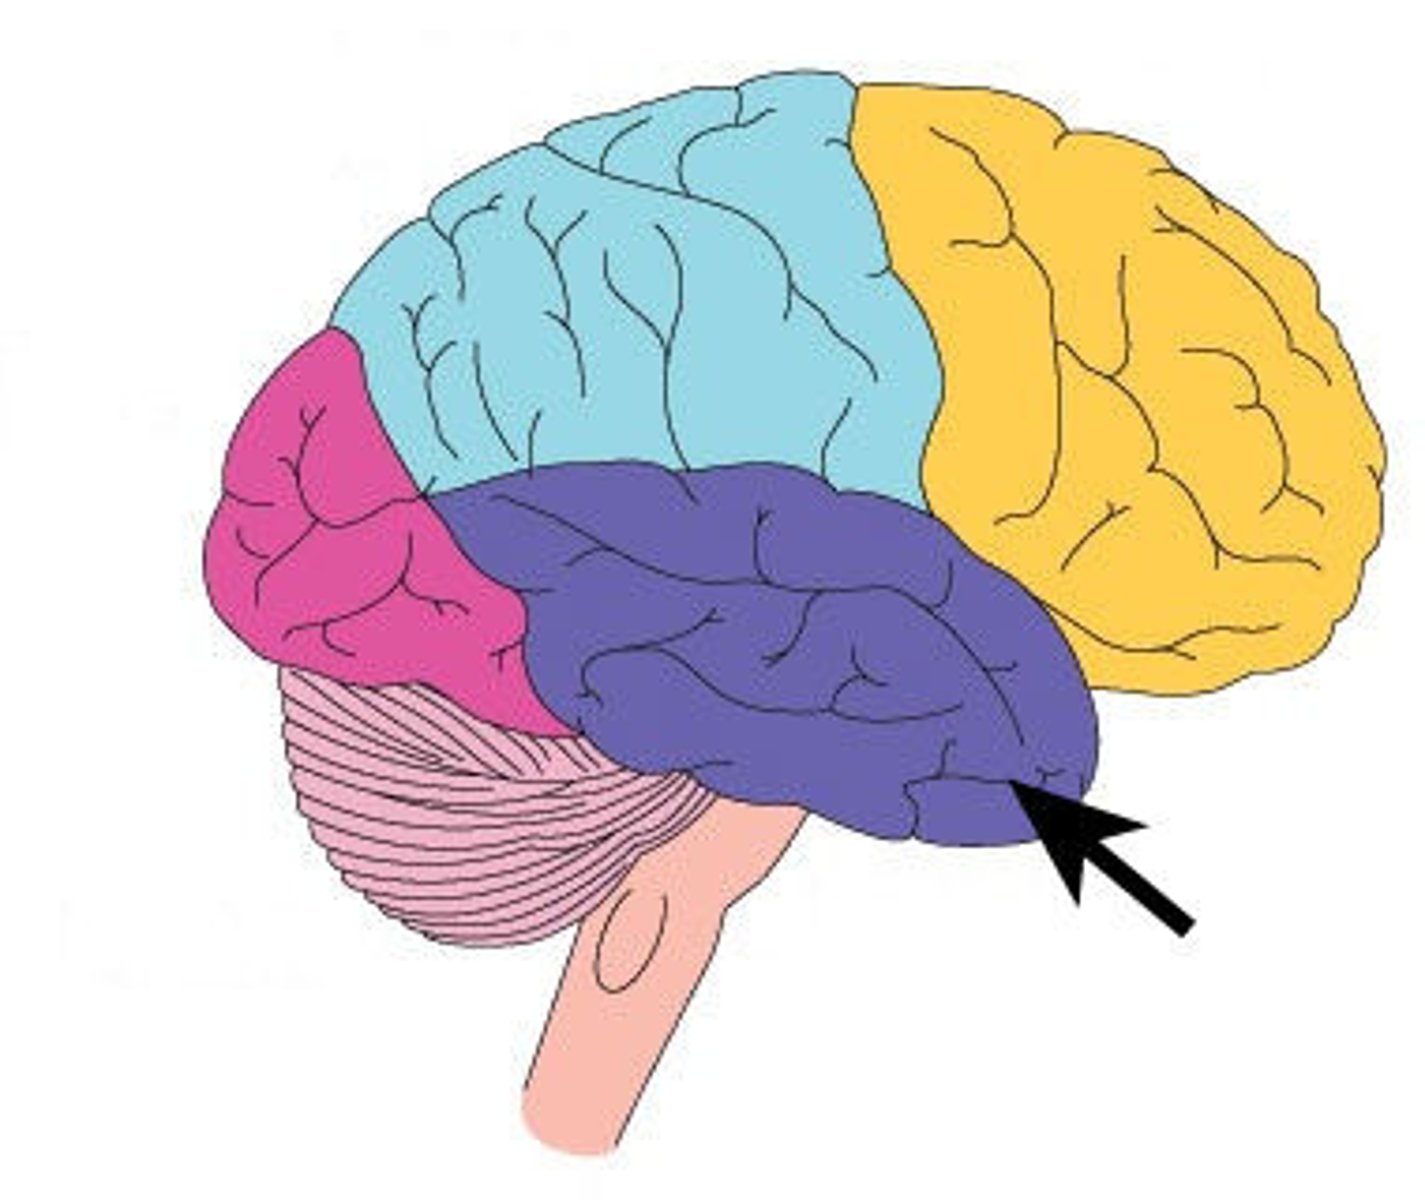

Surface lobes of the cerebrum

Frontal Lobe,

Temporal Lobe,

Parietal Lobe,

Occipital Lobe

Frontal Lobe

Temporal Lobe

Parietal Lobe

Occipital Lobe

Frontal lobe: motor cortex

1) Controls precise or skilled voluntary movements of our skeletal muscles

2) Also learned motor skills (repititious or patterned nature) like playing an instrument or typing

3) Is contralateral: left primary motor cortex controls muscles on right side of body & vice versa